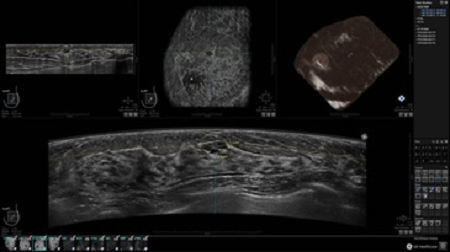

• Получение объемных 3D изображений с возможностью покадрового просмотра

• Алгоритмы обработки изображений: алгоритм однородности изображения ткани (TEA), подавление зернистости, компенсация акустической тени от соска (NSC), определение границ молочной железы (BBD), определение стенки грудной клетки

• Получение изображений в поперечной плоскости (в реальном времени) и в коронарной плоскости (статическая, для указания нахождения соска)

• Отображение объемных 3D ультразвуковых изображений, которые состоят из традиционных поперечных и воссозданных коронарных и сагиттальных проекций

• Возможность отображения полного 3D изображения

• Стандартизованная ориентация изображения: «толстый срез» в коронарной плоскости; поперечная; сагиттальная плоскость; радиальный и антирадиальный поворот изображения; просмотр исключительно области интереса

• Изменяемая толщина среза: 0,5 - 10,0 мм (шаг 0,5 мм)

• Срез: 0,5 - 2,0 мм (шаг 0,5 мм)

• 360 ° APC - отображение области по «любой точке компаса»

• Одновременный просмотр двух изображений для сопоставления в коронарной плоскости